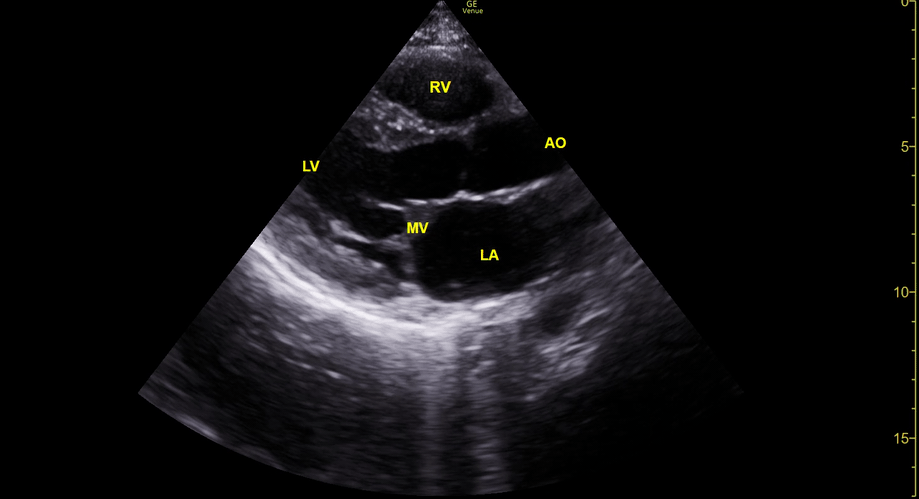

THE VIEWS

The PLAX view is versatile and allows the recognition of multiple landmarks, making it good for visual estimation of LV contractility. It is essential to optimize the view ensuring a true sagittal long axis, as being oblique to the LV chamber may underestimate its size and overestimate its emptying. The PSAX view at the level of the papillary muscles reveals the entire muscular circumference and concentric squeeze of the LV. It is useful to estimate both global function and focal wall motion abnormalities. The A4C view, although technically challenging, provides good insight into the global myocardial function and chamber size.

E-POINT SEPTAL SEPARATION

Active movement of the MV anterior leaflet during diastole, so it nearly touches the septum, correlates with good LV filling and ejection fraction. This can be assessed objectively by measuring the E-point septal separation (EPSS), which is the distance between the septum and the mitral anterior leaflet either in B-mode or M-mode. EPSS < 7mm is considered normal. EPSS is a good surrogate measure of ejection fraction, but it should be used with caution, as septal hypertrophy and mitral valve stenosis can lead to wrong estimations. In the PLAX view, it is important to have the septum lying horizontally flat on the image, as an oblique orientation may result in an overestimation of the EPSS.

Depiction of E-point septal separation: M-mode is used to measure the distance between the open mitral valve and the ventricular septum. Measurements greater than 7 mm are suggestive of depressed systolic ejection. (1. RV free wall, 2. Interventricular septum, 3. Mitral valve, 4. LV free wall). From: The "5Es" of emergency physician-performed focused cardiac ultrasound (11).